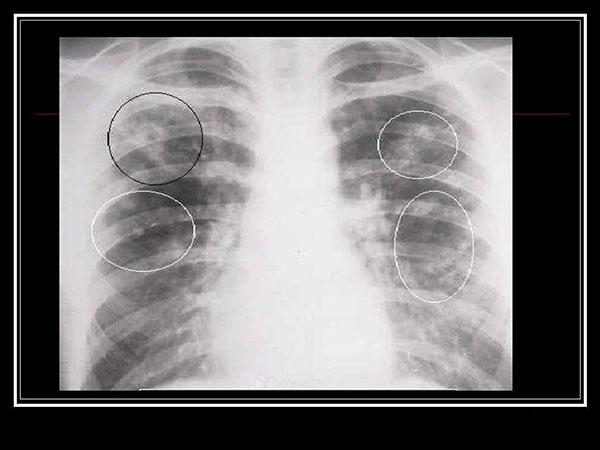

Основа диагностики – инструментальные и лабораторные методы исследования. Рентген показывает слабые либо среднеинтенсивные участки инфильтрации в виде размытых теней, усиление бронхиального и сосудистого рисунка.

Симптомы атипичной пневмонии у взрослых и детей малоспецифичны. Диагноз в основном подтверждается при исследовании биологического материала пациента, который направляется на исследование сразу же, как только врачу становится понятно, что классический протокол лечения эффекта не даёт. Во многих случаях на рентгенологическом снимке просматривается воспалительный процесс в лёгких, но стандартная терапия никакого эффекта не даёт.

Врач может распознать микоплазменную пневмонию на рентгеновском снимке. Лечение проводится медикаментозное, преимущественно макролидами и тетрациклинами.

Атипичная микоплазменная пневмония на снимке